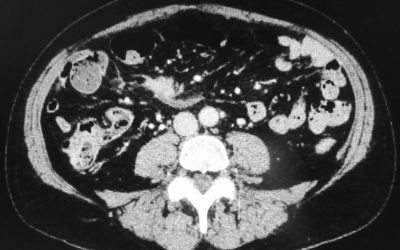

I tumori neuroendocrini del tenue

di Enrico Ganz In questo breve articolo presento un aggiornamento sui tumori neuroendocrini del tenue e descrivo un caso di tumore neuroendocrino dell’ileo, da me trattato chirurgicamente. Non lo esporrò tuttavia nella classica descrizione del “case report”;...